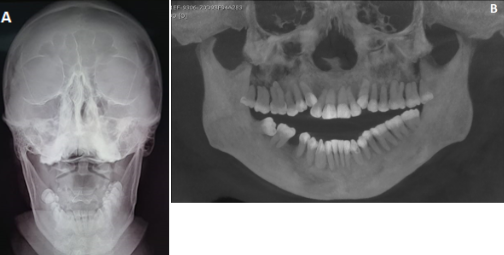

Se trataba de un paciente alerta, cooperador y ubicado en sus tres esferas neurológicas; después de la exploración física dirigida, se observó que el paciente mostraba una desarmonía dentofacial, mordida abierta, incompetencia labial y disoclusión dental. A la palpación bilateral de la ATM se identificaban dos aumentos de volúmenes en región preauricular, de consistencia dura e inmóviles (Ver Figura 1 A).

El paciente exhibía apertura bucal máxima de 46 mm, dentición permanente y mala higiene oral, con presencia de restos de alimento y lengua seborreica. No se pudo determinar su clase molar y canina, pues no era capaz de realizar oclusión dentaria en máxima intercuspidación (Ver Figura 1 B).

Se dispuso de ortopantomografía, radiografía simple lateral y postero-anterior de cráneo, realizadas el mismo día de la consulta. Tras estos procedimientos, se observó ausencia del órgano dentario 46 y una incorrecta posición de los cóndilos mandibulares, que se encontraban anterior a sus eminencias articulares, en lugar de sus posiciones anatómicas normales en las fosas articulares del hueso temporal (Ver Figura 2).

De la misma manera, la tomografía computarizada de macizo facial mostró la mala posición en la que se encontraban los cóndilos mandibulares en relación con sus fosas articulares. No se encontraron zonas hiperdensas circundantes a los cóndilos, por lo que se descartó la probabilidad de anquilosis de ATM (Ver Figura 3).